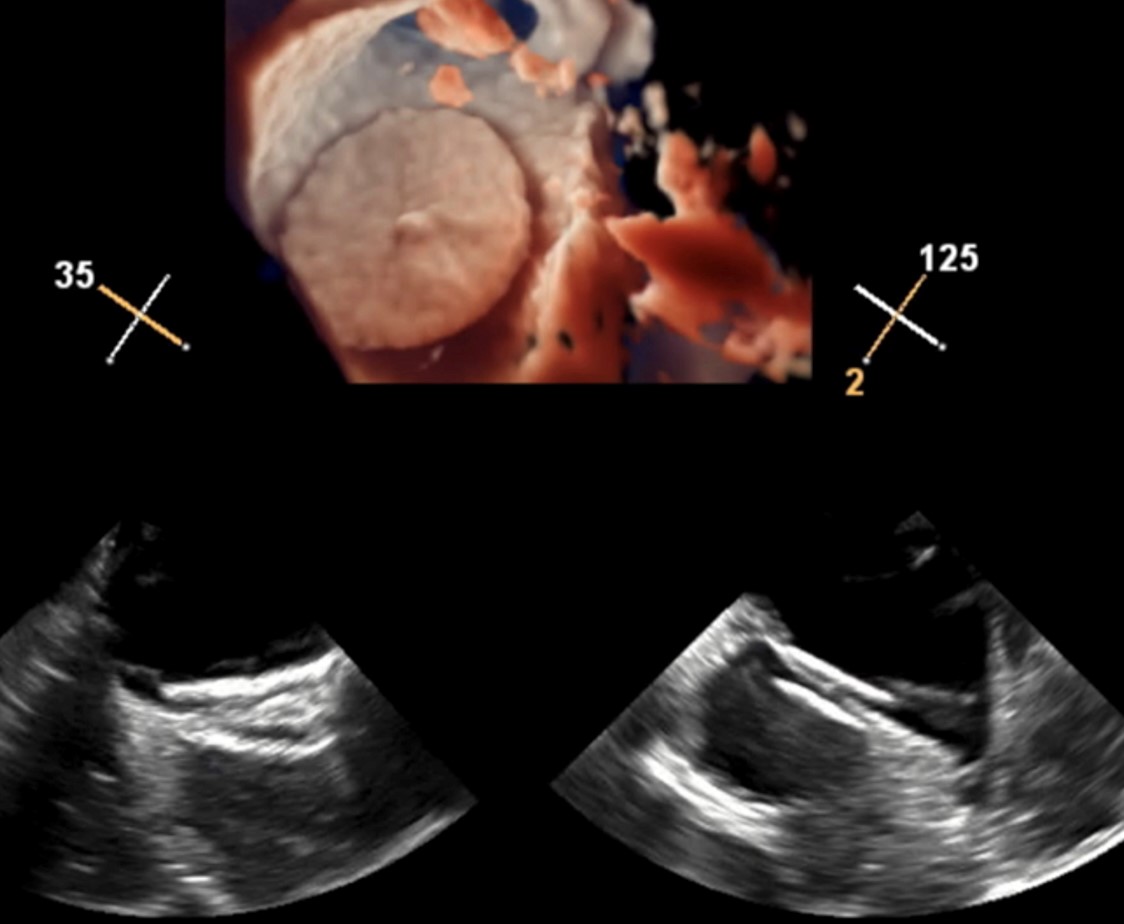

Verschluss eines Persistierenden Foramen Ovale (PFO)

Ein persistierendes Foramen ovale (PFO) ist eine kleine, angeborene Verbindung zwischen den Herzvorhöfen, die sich bei etwa einem Viertel der Menschen nach der Geburt nicht vollständig schließt. Meist bleibt es unbemerkt und harmlos. In bestimmten Fällen, etwa bei einem Schlaganfall ohne erkennbare Ursache (kryptogener Schlaganfall), kann ein PFO jedoch eine Rolle spielen, da kleine Blutgerinnsel aus dem venösen Kreislauf durch die Öffnung ins Gehirn gelangen können.

In solchen Fällen kann ein PFO-Verschluss sinnvoll sein. Dabei wird über die Leistenvene ein Katheter ins Herz eingeführt und unter Bildgebung ein kleines Schirmchen in der Öffnung platziert, das diese dauerhaft verschließt. Der Eingriff dauert etwa eine Stunde, erfolgt meist unter lokaler Betäubung mit Sedierung, und erfordert in der Regel nur einen kurzen Krankenhausaufenthalt.

Der Verschluss kann bei sorgfältig ausgewählten Patienten das Risiko eines weiteren Schlaganfalls deutlich senken. Der Eingriff ist gut verträglich, kleinere Risiken wie Blutergüsse oder vorübergehende Herzrhythmusstörungen sind selten. Die Entscheidung zum PFO-Verschluss wird individuell nach ärztlicher Abklärung getroffen.

2-D und 3-D transösophageale Echokardiographie nach erfolgreichem PFO-Verschluss